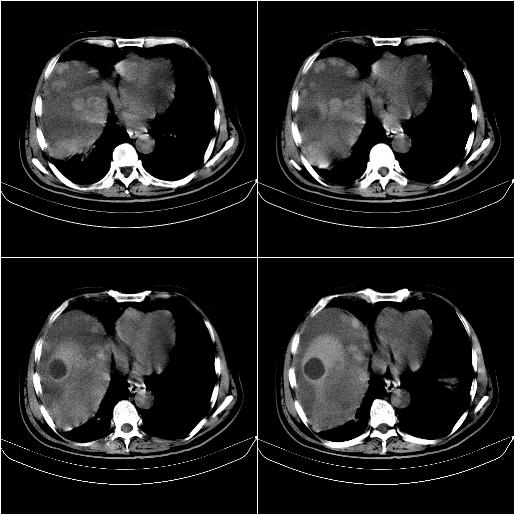

标题: CT21651:M,67Y,肝癌9月,介入术后3月。

m,67y,肝癌9月,介入术后3月。现腹胀、纳差、腹泻。

脾脏转移。。。

1)肝癌介入治疗术后碘油沉积不良。2)门静脉瘤栓形成,腹膜广泛性转移。3)肝硬化,脾大,腹水。4)慢性胆囊炎。